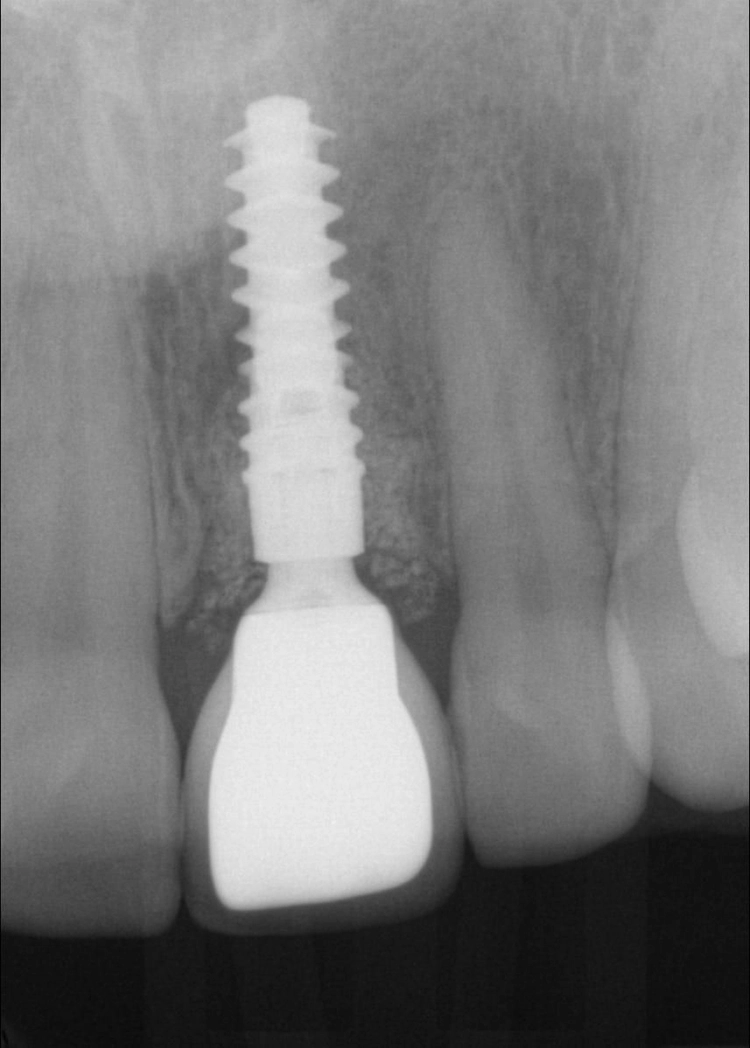

Die Einheilphase verlief komplikationslos. Für die Herstellung der definitiven Implantatkrone wurde eine konventionelle Implantatabformung vorgenommen, um die präzise Passung des Abformpfostens auf dem Implantat am Röntgenbild vornehmen zu können (Abb. 26 und 27).

Theoretisch wäre die digitale Datenerfassung mit dem Intraoralscanner möglich, allerdings sind die Scanpfosten nicht radioopak, so dass eine exakte radiologische Kontrolle nicht möglich ist. Im Dentallabor wurde zunächst das vollkeramische Abutment gefertigt und nach dessen Einprobe die vollkeramische Krone hergestellt (Abb. 28 bis 30). Nach dem Verschrauben der Krone im Mund konnte der Schraubenkanal mit Komposit verschlossen werden. Es zeigt sich eine stabile Situation mit einem gesunden peri implantären Weichgewebe und harmonischem Gingivaverlauf (Abb. 31a und b).